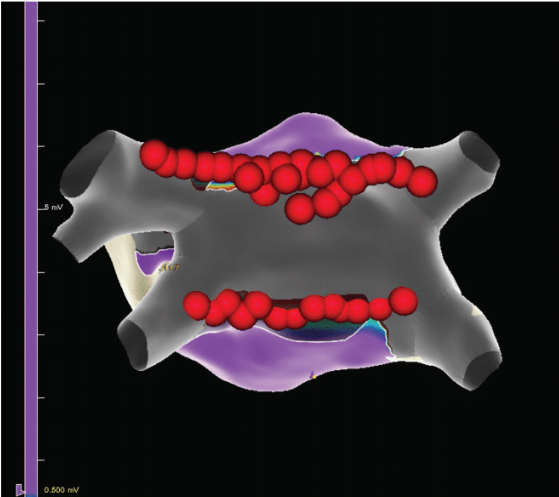

The endocardial portion of the procedure occurred 45 days later in the EP laboratory. The patient underwent routine preoperative TEE to assess

the LA, LA thrombus, and success of the LAA closure. The patient presented in AF. The patient was placed under general anesthesia and successfully cardioverted to sinus rhythm. Radiofrequency (RF) ablation of the CTI with the TactiCath Contact Force Ablation Catheter, Sensor Enabled (Abbott) was performed, which demonstrated medial to lateral block of about 151 ms. Block across the linear ablation line was confirmed with the EnSite X System (Abbott). We then proceeded to the LA via transseptal puncture with the VersaCross Transseptal Platform (Baylis Medical). Mapping of the LA was performed utilizing the Advisor HD Grid Mapping Catheter, Sensor Enabled (Abbott). The pre-LA endocardial ablation map (Figure 2) showed areas of scar creation near the middle of the posterior wall but healthier tissue near the veins, as well as areas of the epicardial region where there was some difficulty. The Advisor HD Grid catheter was then exchanged for the Arctic Front cryoballoon catheter (Medtronic) to allow for single-shot ablation of the PVs. After PVI, the system was exchanged for the Advisor HD Grid catheter and mapping was again performed in the LA. The additional lesion sets from PVI were displayed on the map and the Advisor HD Grid catheter was exchanged for the TactiCath catheter. Linear RF lesions were then made across the roof connecting the left and right superior PVs as well as the floor of the LA connecting the left and right inferior PVs. There were a few areas of presumed epicardial breakthrough points on the posterior wall, and further RF applications in those areas resulted in complete posterior wall isolation (Figure 3). Once complete, another EP study was performed with isoproterenol infusion and no additional arrhythmias were inducible. All catheters and sheaths were removed, and hemostasis was achieved with a figure-of-8 suture. There were no complications from the endocardial portion of the procedure. The patient was ambulatory within 2 hours and discharged home the day of the procedure.